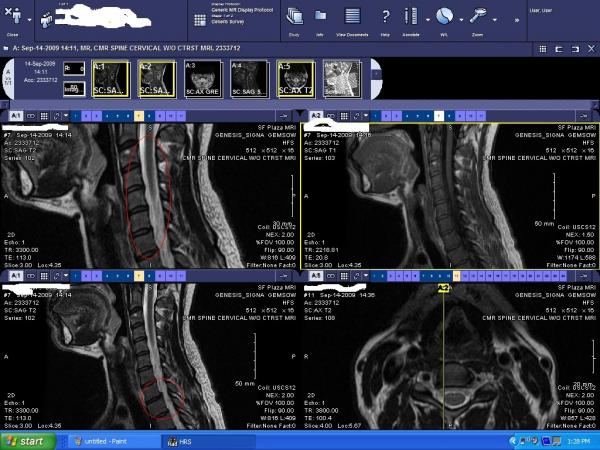

Well, I had a cervical MRI yesterday (because lately I've been experiencing headaches and numbing in my fingers) and of course I don't have the radiologist report yet, but to my untrained eye, it looks like I might have some bulging discs? Anyone care to comment on what you think you see? Hopefully the pic is big enough...

the one axial image seems to indicate a small herniation or protrusion to the right side -- is the tingling / numbness in your right arm?

The other images seem to show some protrusion in your thoracic spine, based on what is circled

however, would obviously defer to competent medical authority for the definitive explanation